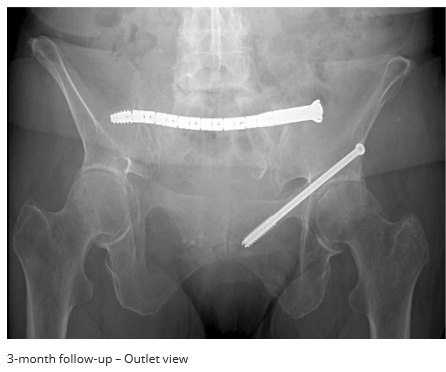

At 3 months, the patient`s fractures were healed and the patient was asymptomatic.

- Safe placement of transiliac-transsacral fixation in S1 of a dysmorphic pelvis would not have been possible with a straight screw.

- A CurvaFix implant in S1 provided fixation without need for lumbopelvic stabilization with spinal implants.